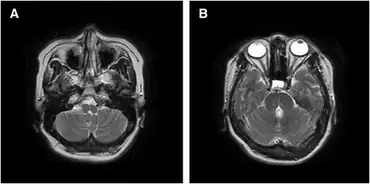

Hemiplegia is identified by clinical examination by a health professional, such as a physiotherapist or doctor. Radiological studies like a CT scan or magnetic resonance imaging of the brain should be used to confirm injury in the brain and spinal cord, but alone cannot be used to identify movement disorders. Individuals who develop seizures may undergo tests to determine where the focus of excess electrical activity is.[18]